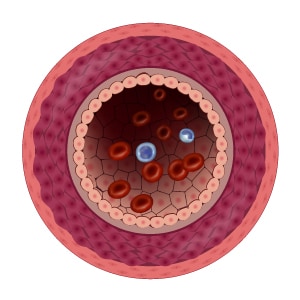

Your heart is like an engine, pumping out blood through your blood vessels to the rest of your body, keeping your organs up and running.

With clean and elastic blood vessels, blood, oxygen and nutrients can reach their destinations easily and quickly.